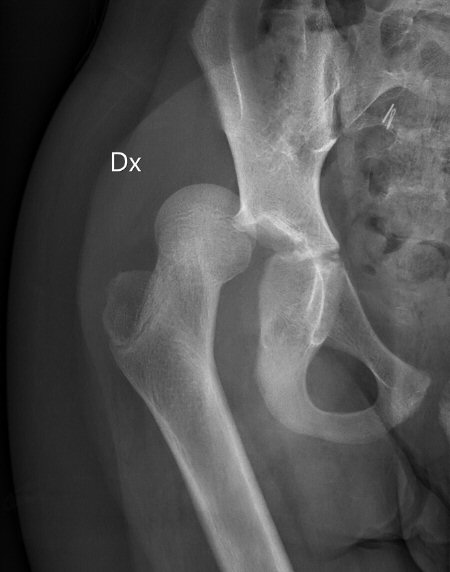

Exempel på höft hos 10-åring som luxerat efter lindrigt trauma

Vid ålder < ca 10 år kan det räcka med lindrigt trauma, exempelvis fall vid idrottsutövande, vid ålder > 10 år krävs ofta högre energi. [1, 2]